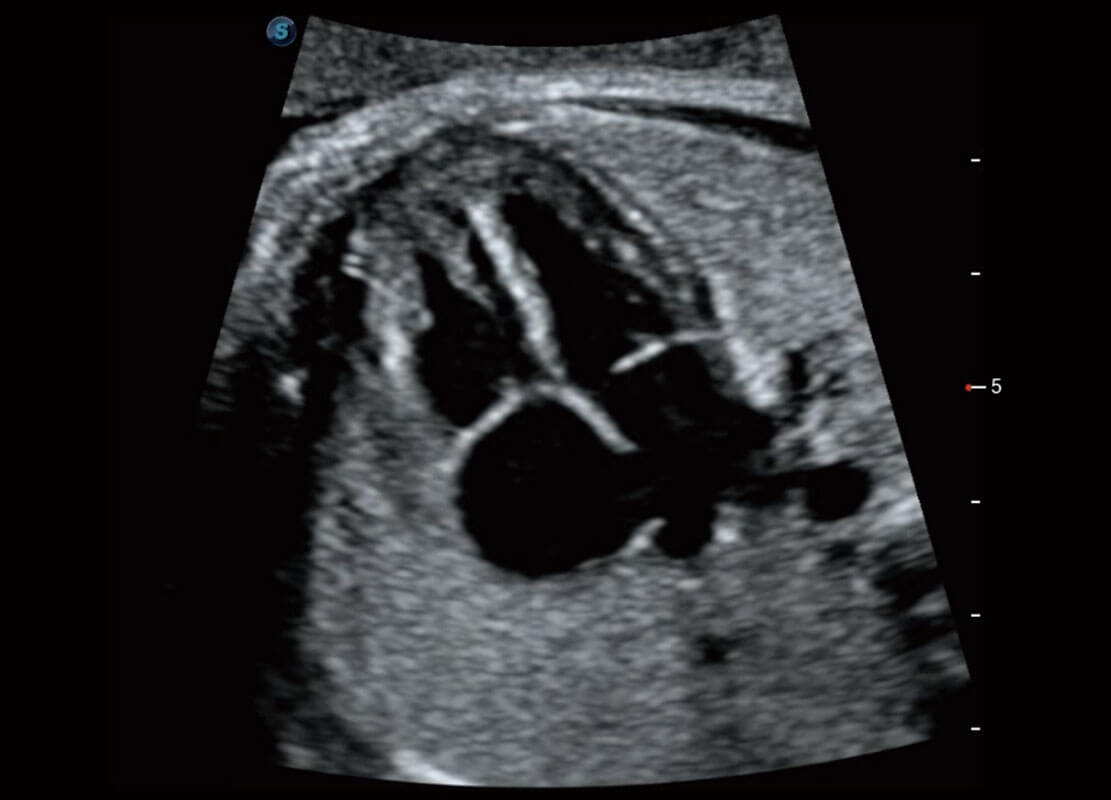

腔内妇科-卵巢

腔内三维-宫内节育器